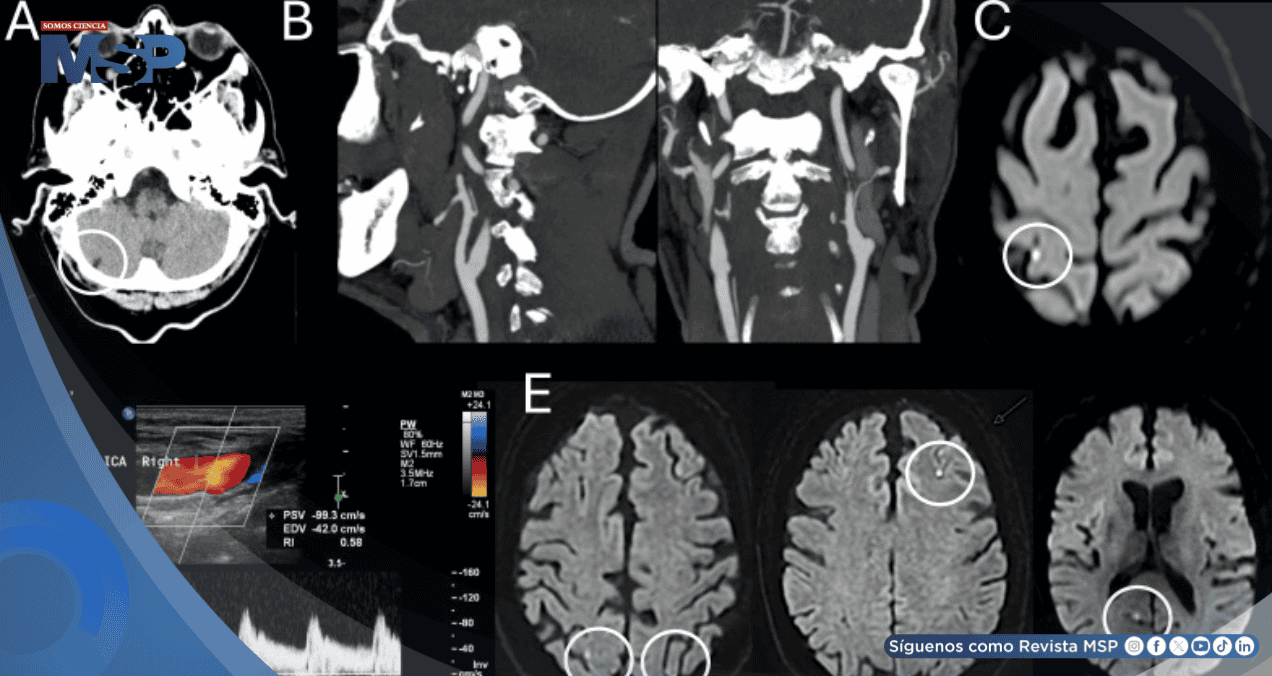

Seis meses antes, este mismo paciente había sido diagnosticado con un infarto cerebeloso derecho crónico y asintomático, sin que se identificara una fuente embólica clara. En esa ocasión, se había descartado un estado protrombótico relacionado con su tumor y se había iniciado tratamiento con un antiagregante plaquetario y estatinas.

Mientras que la tomografía computarizada inicial solo mostró el viejo infarto cerebeloso conocido, la resonancia magnética cerebral reveló el hallazgo decisivo: una pequeña lesión isquémica aguda (visible en secuencias de difusión) localizada en la circunvolución poscentral del lóbulo parietal derecho, específicamente en una zona conocida como unión parieto-occipital (PO).

Este infarto "puntiforme" o "en gota" correspondía al territorio de la arteria cerebral media.

Se diagnosticó al paciente con un accidente cerebrovascular isquémico agudo en la corteza parietal derecha (unión PO), cuya etiología final se clasificó como embólica de origen indeterminado, a pesar de exhaustivos estudios para buscar una causa.

El manejo del paciente se intensificó con doble antiagregación plaquetaria temporal. En el seguimiento, sufrió otros eventos isquémicos cerebrales menores asintomáticos, lo que reforzó el diagnóstico de una fuente embólica. Finalmente, se cambió su anticoagulación a warfarina, manteniéndose estable.